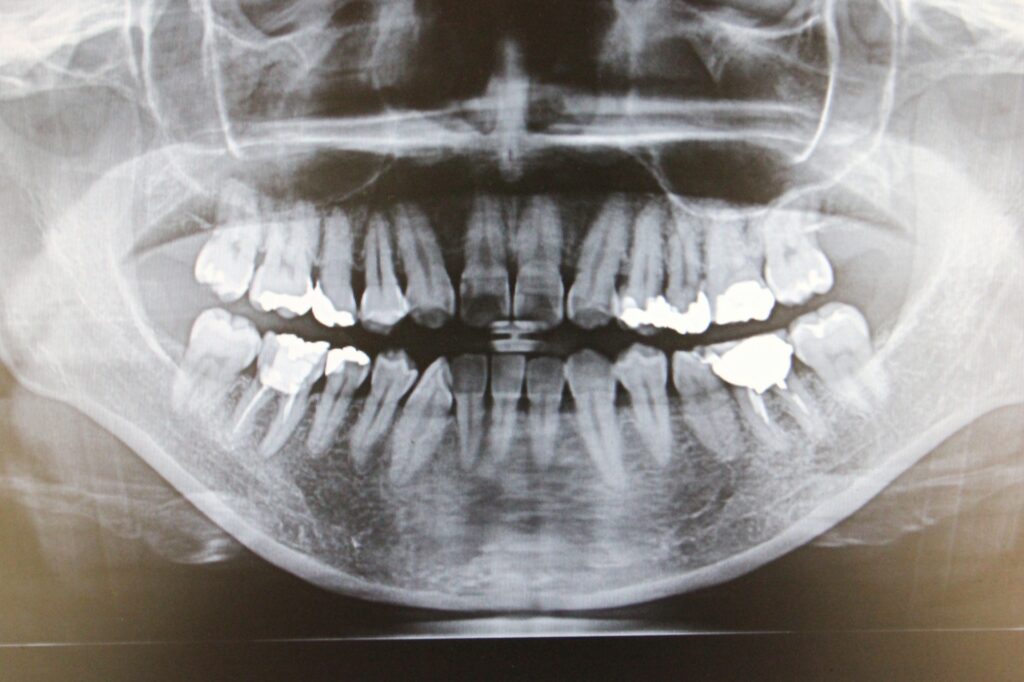

🦷 パノラマレントゲン・

10枚法X線写真(レントゲン)

パノラマレントゲン

歯周病の治療計画を立てる上で、レントゲン撮影は目に見えない「歯を支える骨」の状態を知るために欠かせない検査です。

当院では、主に「パノラマレントゲン」と「デンタルX線写真(10枚法など)」の2種類を撮影します。

1. パノラマレントゲン(お口全体を映す写真)

パノラマレントゲンは、お口全体の状態を一枚の大きな写真として撮影するものです。

これにより、歯周病の進行状況だけでなく、顎の関節や親知らず、お口全体の骨の量とバランスを俯瞰的に把握できます。

例えるなら、「お口全体の地図」のような役割を果たし、これから行う治療の全体像と優先順位を決定するために必要不可欠です。

このように、広範囲を把握する「パノラマ」と、詳細を分析する「デンタル」を組み合わせることで、あなたの歯周病の状態を診断し、最適な治療計画をご提案しています。